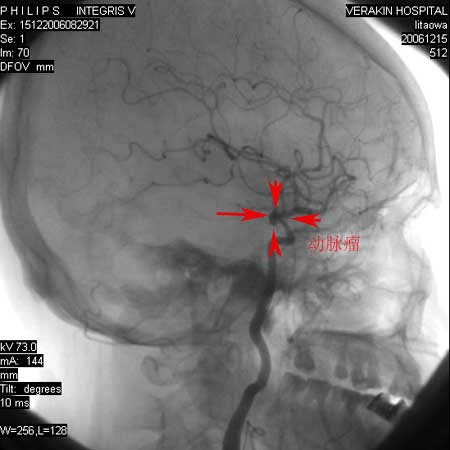

标题: DSA0063:颈内动脉血管造影

女,60岁,行全脑血管造影,图片较多,选了左颈内动脉造影100幅图中的10幅图片,请包涵。

支持后交通动脉起始部动脉瘤。

后交通动脉瘤.

另外:大家讨论的\"动脉瘤\"实际是血管分支重叠影像,本帖单侧颈内动脉仅见轻度动脉硬化性狭窄..参考旋转dsa请连接:http://www.sdhct.com.cn/radinet/read.php?tid=19818